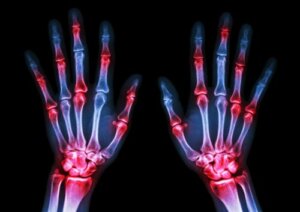

Rheumatoid arthritis is a chronic disease characterized by inflammation and deformities of the joints and the surrounding tissue. This type of arthritis is very common among adults who are over 60, although there are certain cases when it develops at earlier stages.

It often affects areas such as the knees and hands. However, it can also affect other parts of the body, including some muscles and tissues.

Rheumatoid arthritis is a disease that typically affects several different joints, especially in the hands and knees.

Symptoms, family history, and X-ray analysis are some of the methods that are used to identify it.